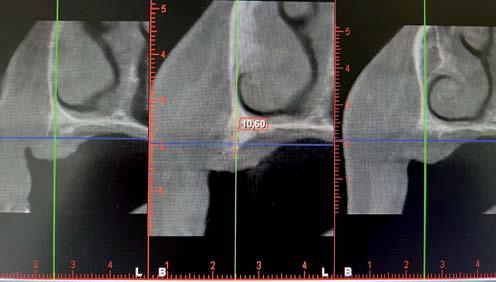

Aún así, existen hoy en día situaciones en las que la inserción de un implante corto o extra-corto no es posible de forma directa, cuando existe un volumen óseo residual por debajo de los 5 mm, existiendo en estos casos una nueva alternativa terapéutica a la elevación de seno convencional que es la elevación de seno transcrestal (14-15).

En esta técnica se accede a través de la cresta mediante la confección de un neoalveolo generado por fresado al seno maxilar despegándose la membrana desde este neoalveolo e insertándose el implante corto o extra-corto con o sin injerto asociado (en función del volumen en altura que se pretende ganar) (14-15).

Este procedimiento, con numerosas modificaciones en cuanto a su secuencia de fresado, tipo de fresas y tipos de injertos a utilizar, se encuentra implantada con éxito entre las técnicas quirúrgicas para el abordaje del maxilar

superior posterior con déficit de altura. Como en muchas otras disciplinas de la Medicina, estos dos procedimientos (elevación de seno por abordaje lateral y elevación de seno transcrestal) coexisten en algunos pacientes. Esto es debido principalmente a la incorporación de la nueva variación del procedimiento en un paciente en el que, previamente, se había realizado el procedimiento anterior, debido a que en el primer abordaje la técnica más novedosa aún no se encontraba presente (16, 17).